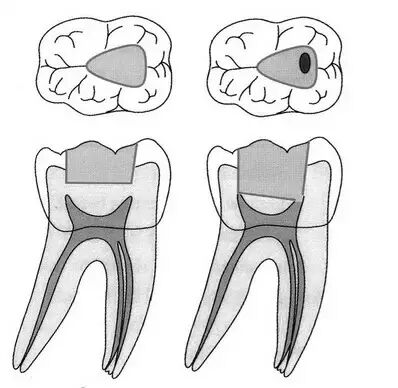

另外Weine对根管结构的分类,我觉得很是不错,确实很简明实用。

Ⅰ型 从根管口至根尖为1个根管(图a)。

Ⅱ型 2个独立的根管自根管口发出,在根尖上方合并成1个根管(图b)。

Ⅲ型 2个独立的根管分别开口于2个分开的根尖孔(图c)。

Ⅳ型 1个根管自根管口发出,在根尖上方分成2个独立的根管并开口于2个根尖孔(图d)。

其他人还有一些补充,其实很少见,吴有农和岳保利的分类很全面,但过于复杂,临床应用不太方便,到是做一些研究的时候很好用。